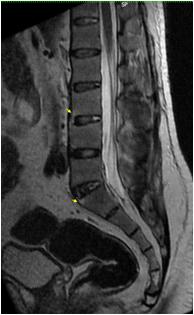

Radiological imaging was done in all the cases. USG findings revealed solitary masses in 45 cases (80.35%) and diffuse masses in 11 (19.64%). Solitary masses were around 45 in number out of which 30 were diagnosed as HCC. Right lobe had around 30 (66.7%) whereas left lobe had 15 (33.33%) masses respectively. Maximum (SOL’s) observed showed hyper-echogenicity present in 43 cases (76.78%). Heterogenous echotexture was observed in 6 cases (10.71%) (Fig 1).

CT scan was done in two patients which showed multiple well defined hyperdense lesions and hypodense lesions in another patient. Cyto-radiological correlation of hepatic masses was seen in 94% cases (Fig 2).

Fig 1 — USG liver showing well defined heteroechoic lesion in left lobe

Fig 2 — CT liver showing multiple enhancing focal hepatic lesions suggestive of metastasis